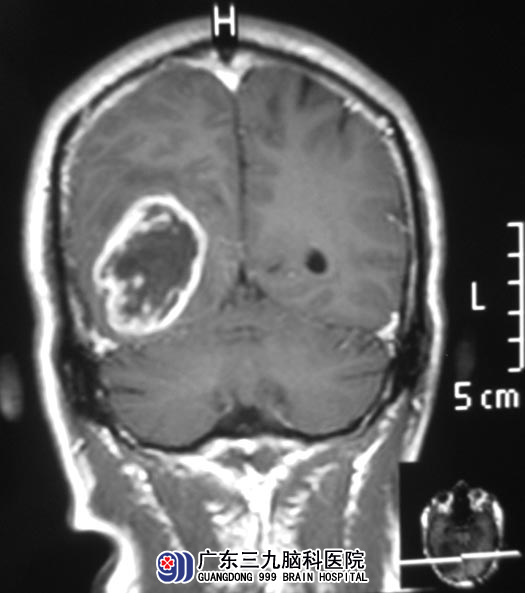

转上一级医院CT检查提示右侧枕叶病变;广东三九脑科医院头颅MR检查提示病变大小约6.6cm×3.4cm×3.1cm,考虑恶性胶质瘤可能性大。综合神经外科 鲁明主任告诉温先生的家人,枕叶是最高级的视觉分析器,即所谓的“视觉中枢”,枕叶肿瘤的主要临床表现为视觉方面的障碍。http://www.999brain.com/

▲手术前